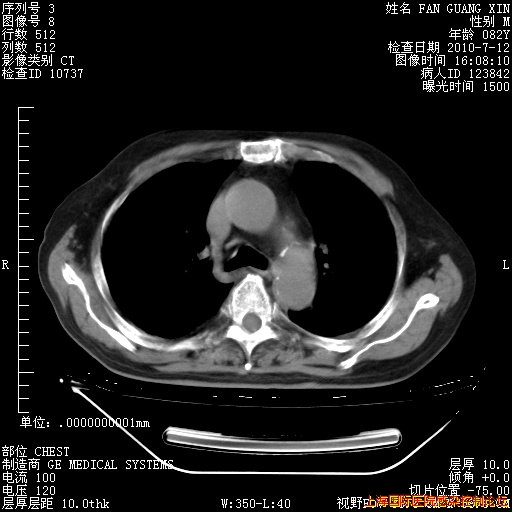

今天复查CT

今天CT

整整相隔30天的肺部CT好像有所好转啊。甲强龙减量第3天,需要观察体温。